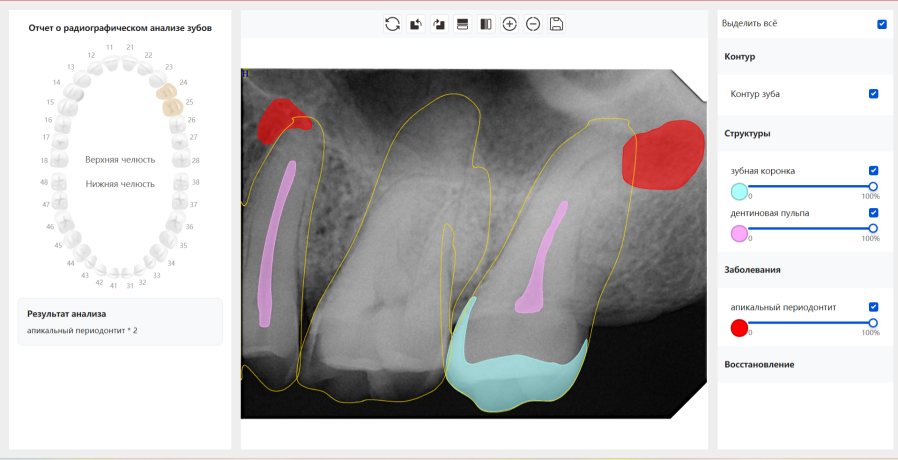

CR/DR 牙齿分割阶段记录

当前进展

- 完成了 CR/DR 牙齿相关分割训练

相关测试

遇到的问题

- 训练过程中出现过 mask 下移问题

- 部分结果会出现 box 填充异常

- mask 边缘仍然有比较明显的锯齿感

第二版算法问题测试

Updated: 2026-04-13(更新日期)

| 第一版 | 第二版 | 是否解决 | |

|---|---|---|---|

![]() | ![]() ![]() 边角识别有问题 龋齿识别不全 牙髓识别不全 | ![]() | 解决 |

![]() | ![]() 边角识别有问题 识别信息有误 自查(牙冠识别不全) | ![]() | 解决 |

![]() | ![]() ![]() 边角识别有误 大范围填充识别遗漏 | ![]() | 解决 |

![]() | ![]() 识别信息不全 | ![]() | 解决 |

![]() | ![]() ![]() 边角问题 牙胶识别不全 牙冠识别不全 | ![]() | 解决 |

![]() 换图片 | ![]() | ![]() 牙冠部分稍微白了一些就识别成小范围修补,部分判断异常 | 部分解决,修复类略敏感,牙冠部分稍微白了一些就识别成小范围修补,部分判断异常。 |

![]() | ![]() ![]() 牙冠识别不全 牙髓不全 根尖炎龋齿识别有误 | ![]() | 解决 |

![]() | ![]() | ![]() | 解决 |

![]() 换图片 | ![]() | ![]() | 解决 |

![]() | ![]() 牙冠识别有误 | ![]() | 解决 |

![]() 换图片 | ![]() ![]() 边角识别有误 | ![]() 修复类敏感 | 部分解决,图像过白,导致修复类判断异常。 |

![]() 换图片 | ![]() 牙冠识别不全 | ![]() 修复类敏感 | 部分解决,图像过白,导致修复类判断异常 |

结论:修复类出现了不鲁棒的情况,后续需要加入轮廓的扩充数据进行增强。